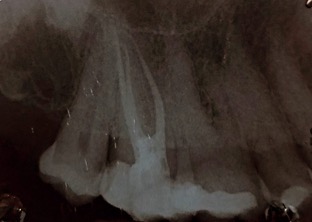

Una corretta terapia canalare con un perfetto sigillo a livello degli apici delle radici è fondamentale. I denti devitalizzati impropriamente possono creare ulteriori problemi che poi andranno a ripercuotersi sulle cure effettuate successivamente come le ricostruzioni e le corone protesiche con conseguente fallimento del piano terapeutico.

Capita spesso di incontrare denti già devitalizzati in maniera impropria che necessitano, seppur asintomatici, di essere ritrattati per evitare che i granulomi infetti visibili radiograficamente si evolvano riassorbendo tutto l’osso sottostante.